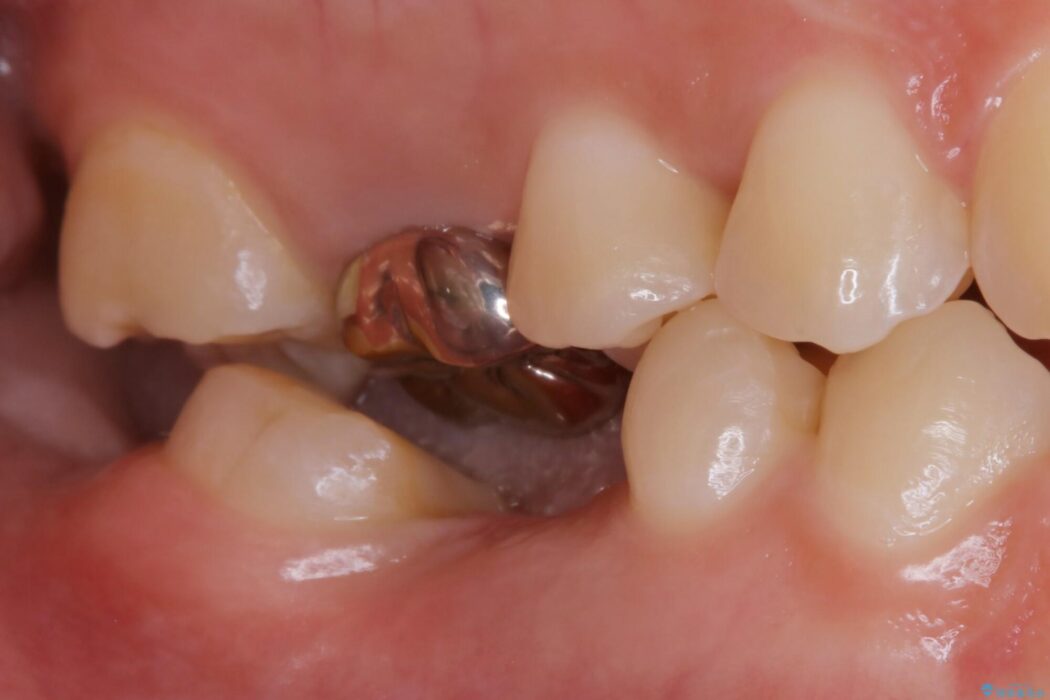

右下奥歯が欠損しているためブリッジでの補綴治療をしたいとの主訴で来院されました。

診査した結果、欠損した状態で長期間放置していたことが原因で最高峰の奥歯が欠けた部分に向かって傾斜してしまっていました。

この状態のままブリッジ治療へと進んでしまうと神経が露出する可能性が否定できないため、まずワイヤー装置による部分矯正で歯軸を通常位置へ戻してから補綴治療を行うこととしました。